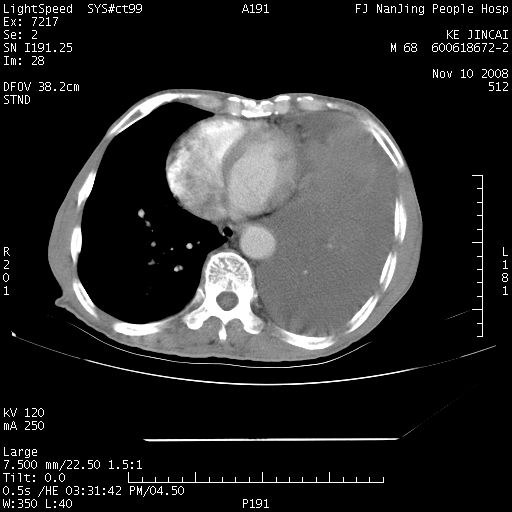

是个很有看头的病例,咋人气那么不旺?没多少人兴趣呢?这个病例几大怪:1   恶性肿瘤侵犯心肌左房怪,心肌一般不会被恶性肿瘤侵犯吧?2   左下肺均匀实变怪,内无含气,有别一般不张实变,含气肺泡完全为液体取代,而非一般不张实变的肺萎陷,冷不丁还以为是肿大的脾脏3   肿瘤本身怪,像tb肺不张4   这么有看头的病例没人气怪。呵呵。

左肺恶性肿瘤侵犯肺动脉,左心房内瘤栓,胸膜转移。

左肺恶性肿瘤侵犯肺动脉,左心房内瘤栓,胸膜转移,少见,学习了。